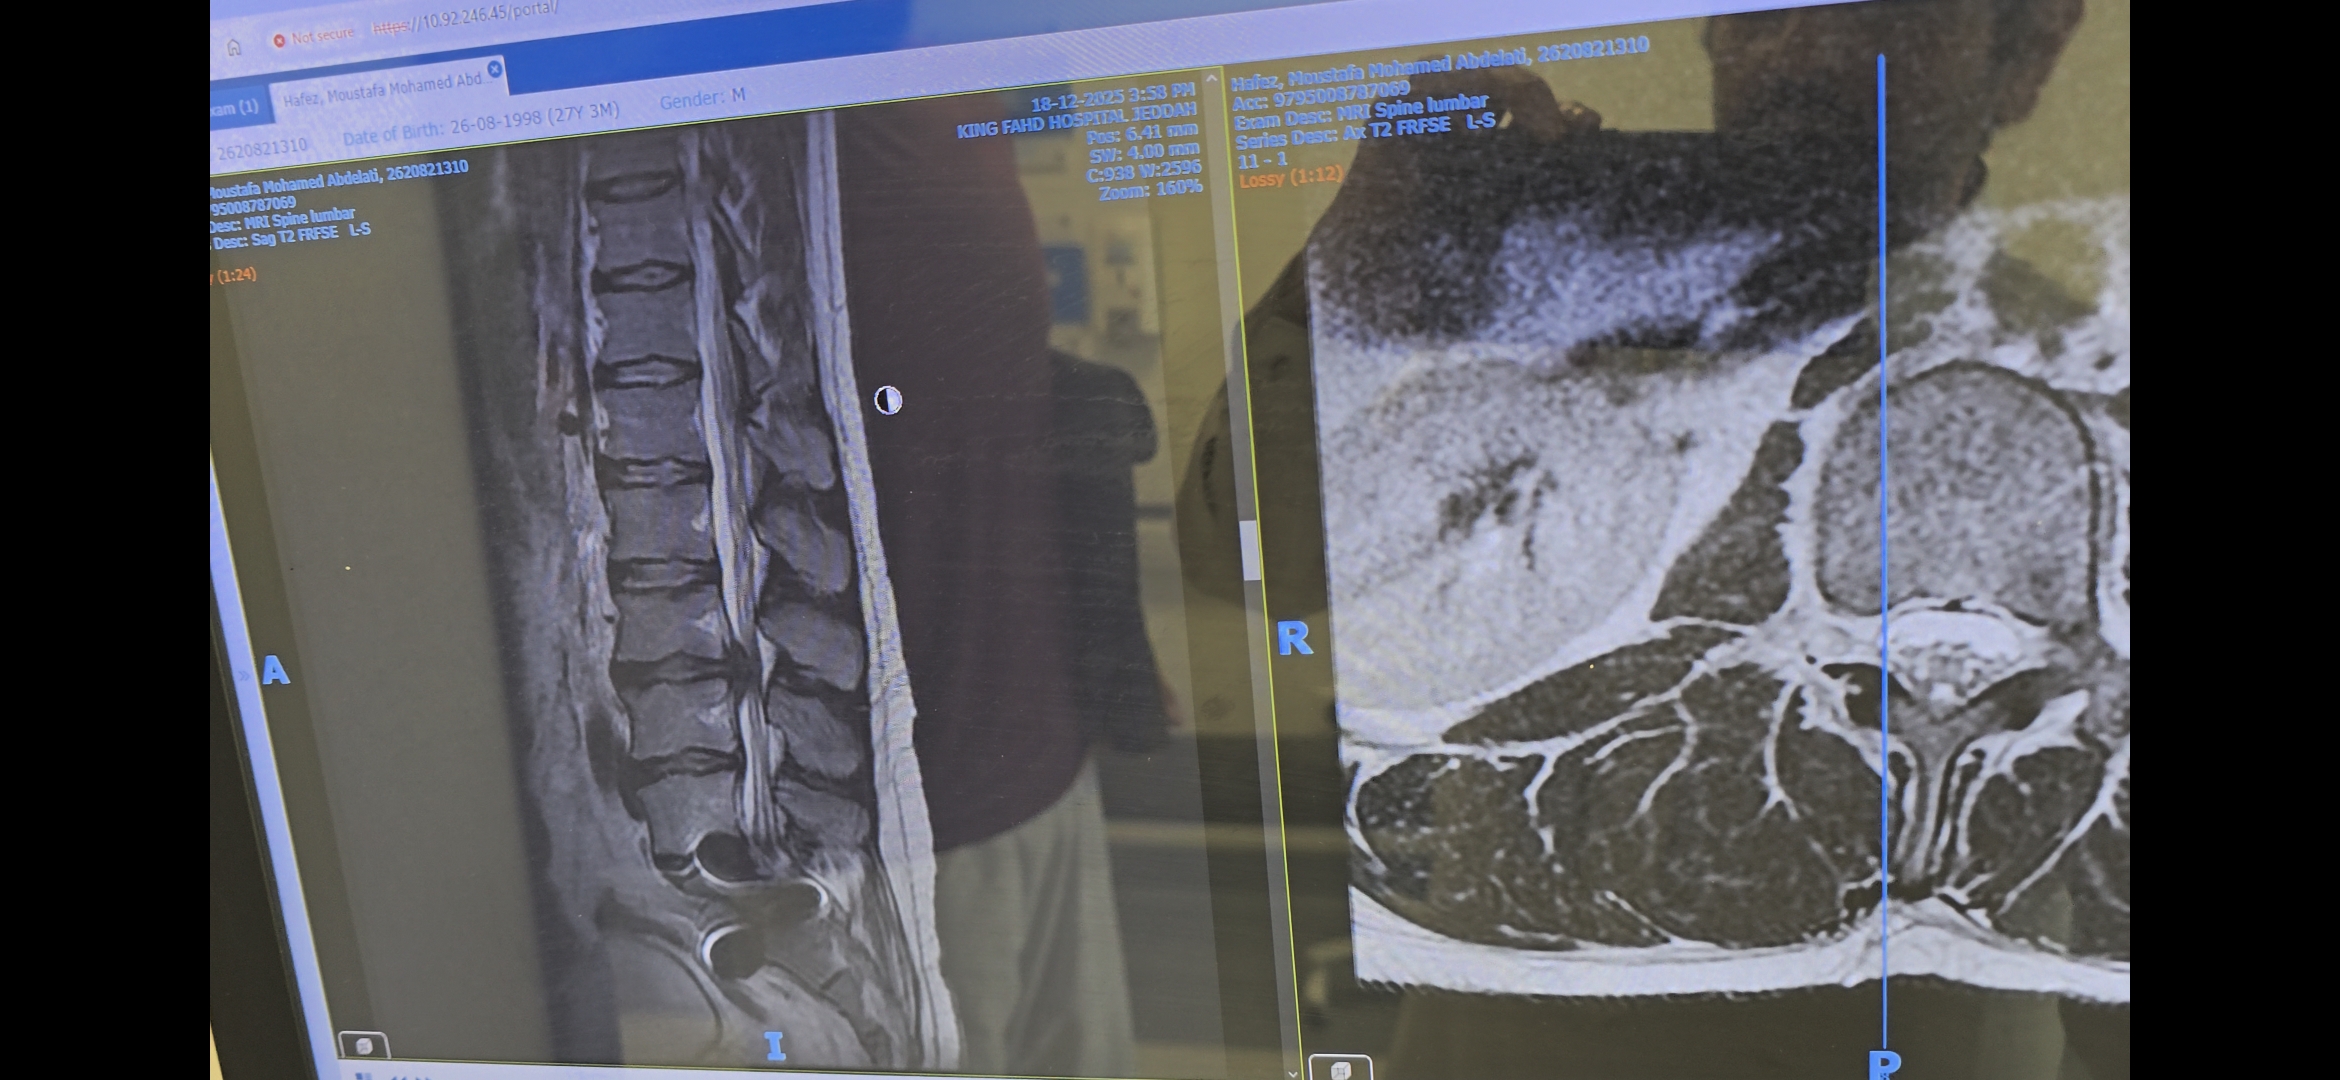

ضعف شديد في الساق وعدم القدرة على المشي ومشكلة بالفقرات القطنيه

اذا كانت اعراض الديسك او الانزلاق الغضروفي منحصرة في الالم المحتمل فقط يمكن الاكتفاء بالمسكنات او العلاج الطبيعي ، لكن عند وجود اعراض اخرى مثل ضعف في الاطراف او مشاكل بولية ينصح بالعملية لتجنب حدوث اعتلات عصبية دائمة